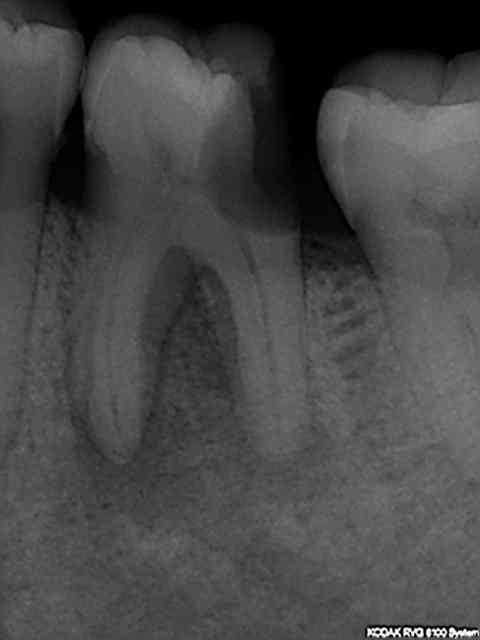

Meme en mode Bw rétro coronaire (capteur horizontal) il est impossible d'avoir toutes les molaires et prémolaires avec un kodak 6100 meme avec 4 clichés (Je ne comprend pas d'ailleurs le capteur semble couvrir toutes les dents) Il manque la 7 ou la 4. 8 clichés sont donc nécessaires (contre 12 en rétro alvéolaires capteur vertical).

Une rétro alvéolaire a été réalisé en sus pour la 37 bien qu'elle ne présente pas de "signes d'appels". Une magnifique endo révélée comme d'hab, le patient est éclairé quant à la survenue d'un éventuel problème. On peut se poser des questions également sur la pertinence des micro classes 1 amalgame sur 46 et 47 a moins que ce soit la conséquence d'un comportement "imaginatif " cher à Catherine M pour rentabiliser les soins opposables.

Sur la 26 ce qu'il faut faire, sur la 27 ce qu'il ne faut pas faire. Ca va rentrer oui ou non ?-))